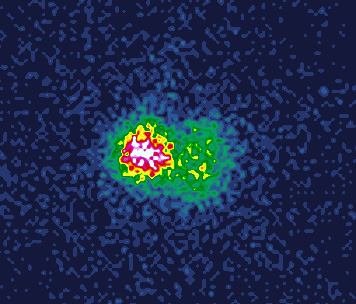

1. Рисунок 1. Планарная сцинтиграфия щитовидной железы с 99mTc-пертехнетатом от 29.11.2019 г.

Тема

Тип Исследовательские инструменты

Посмотреть (201KB)